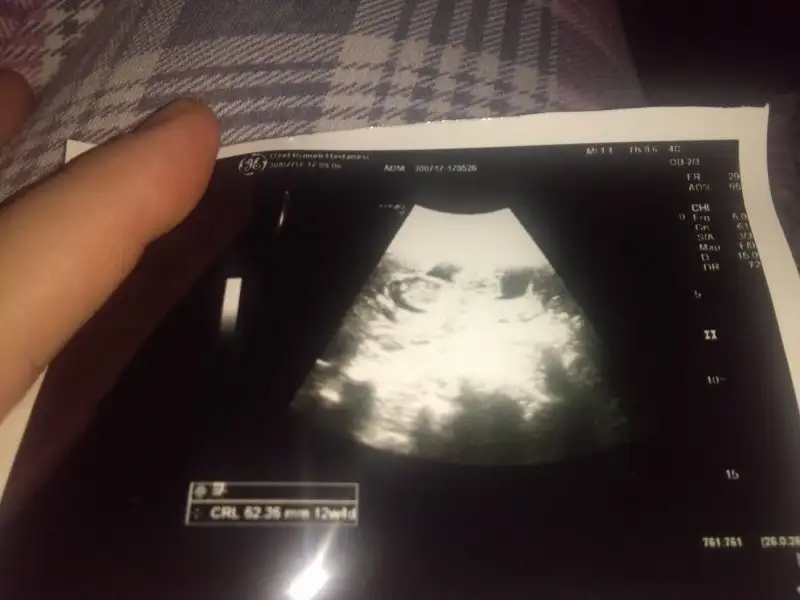

Cnm geç kaldım bıraz siteye giremedim simsi girdim hem 11+4 hemde 12+4 paylaşıyorum bir bak sana zahmet en son resim 11+1 di sanırım12+ canim